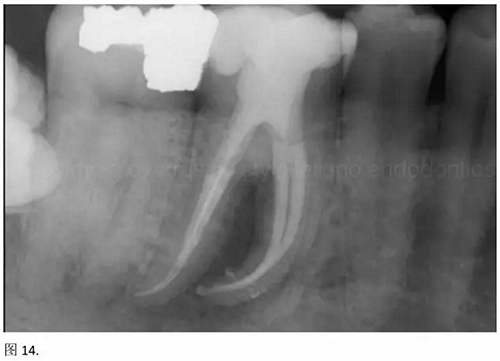

結(jié)論:本文的目的是描述一種旨在優(yōu)化根管根尖部分預(yù)備的預(yù)敞技術(shù)。根管頸部或冠方的早期預(yù)敞對(duì)于減少初尖銼直徑和根尖部根管直徑之間的差異至關(guān)重要。大量研究表明,手用或機(jī)用器械預(yù)敞根管能顯著減少器械折斷的發(fā)生率。下一篇文章將描述如何建立可重復(fù)的引導(dǎo)路徑。而引導(dǎo)路徑是指鎳鈦器械可沿著光滑根管壁輕易地滑行至工作長(zhǎng)度的通路。